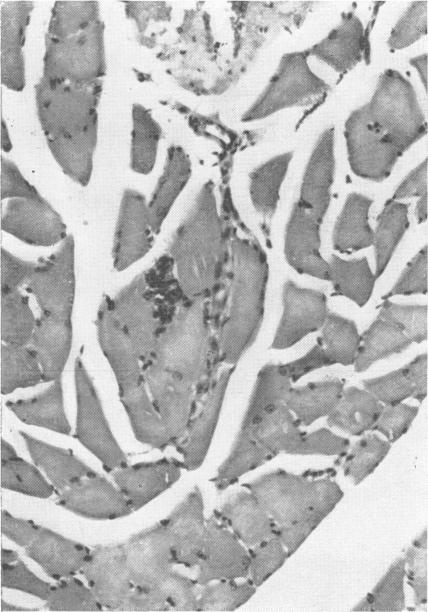

Toxic polyneuritis in Bombay due to ortho-cresyl-phosphate poisoning.

J Neurol Neurosurg Psychiatry. 1962 Aug;25(3):234-42. doi: 10.1136/jnnp.25.3.234.